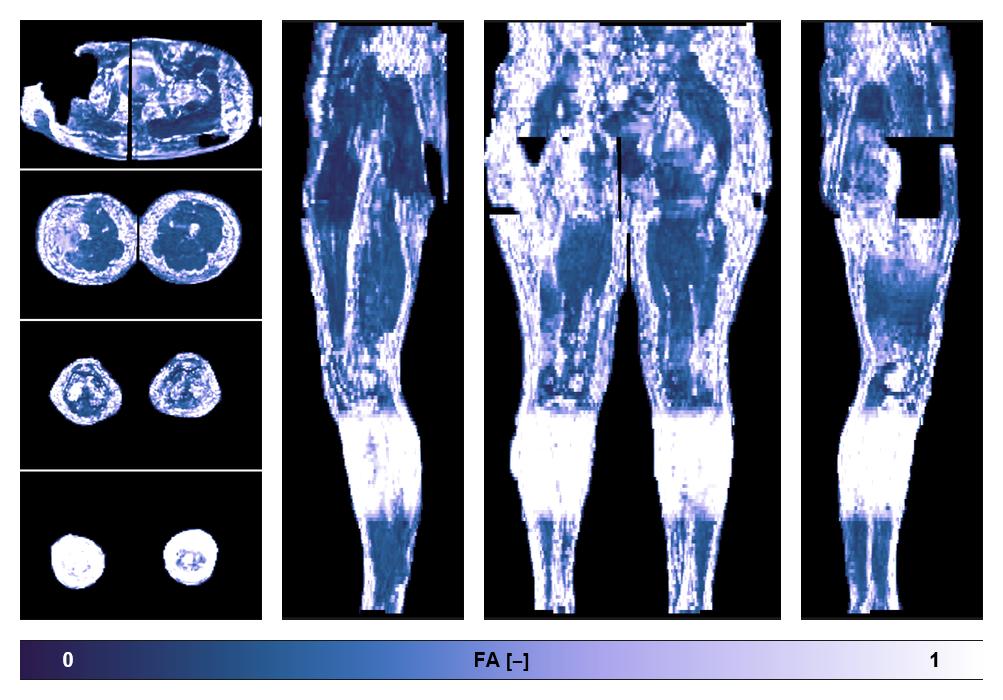

• Fractional anisotropy

IVIM corrected whole leg muscle fractional anisotropy obtained from diffusion tensor imaging.